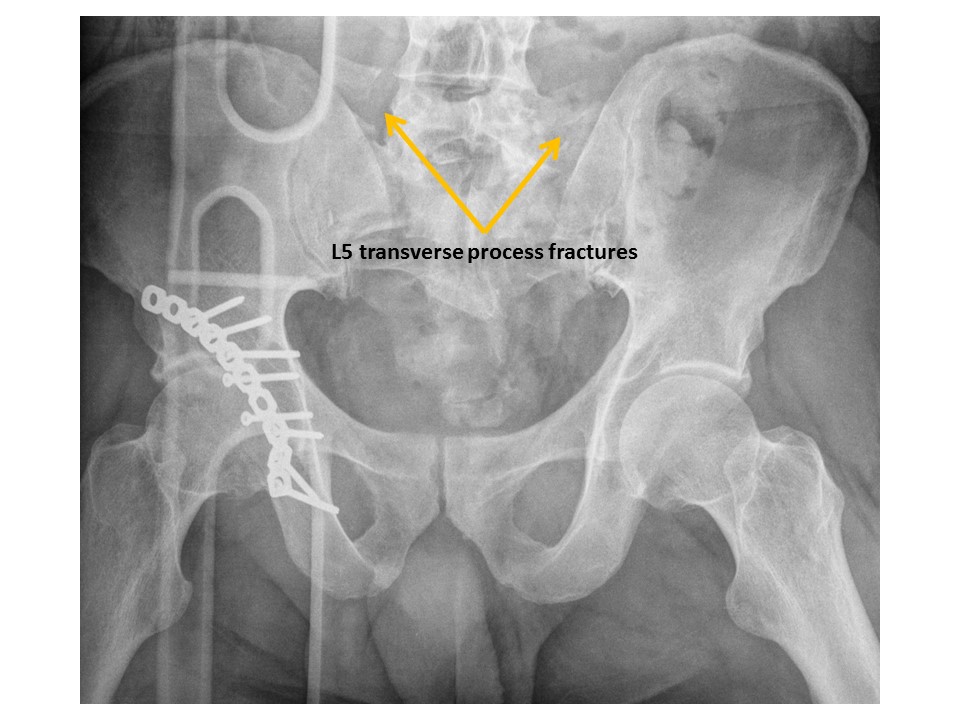

VISUALIZED LUMBAR SPINE

There are transverse process fractures. [Yes/No]